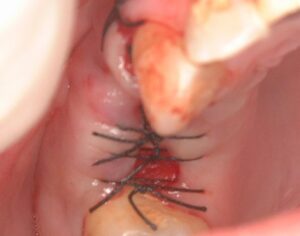

縫合を終えたところです。